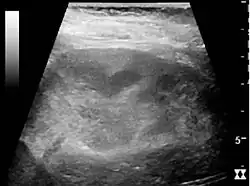

Ultrasound findings that indicate pyelonephritis are enlargement of the kidney, edema in the renal sinus or parenchyma, bleeding, loss of corticomedullary differentiation, abscess formation, or an areas of poor blood flow on doppler ultrasound.[21] However, ultrasound findings are seen in only 20–24% of people with pyelonephritis.[21]

Chronic pyelonephritis with reduced kidney size and focal cortical thinning. Measurement of kidney length on the US image is illustrated by ‘+’ and a dashed line.[20]